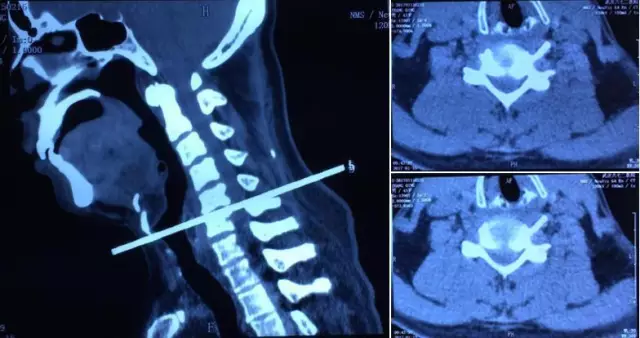

术前CT:提示C5/6椎间盘突出,稳定性尚可,局部椎间盘钙化和后纵韧带骨化并不严重,为脊柱内镜适应症。

术后CT:提示施术部位准确,减压充分。术后3天患者恢复情况良好,术后患侧上肢肌力大为改善,前臂原放射痛症状缓解,手指残余少量麻木感。